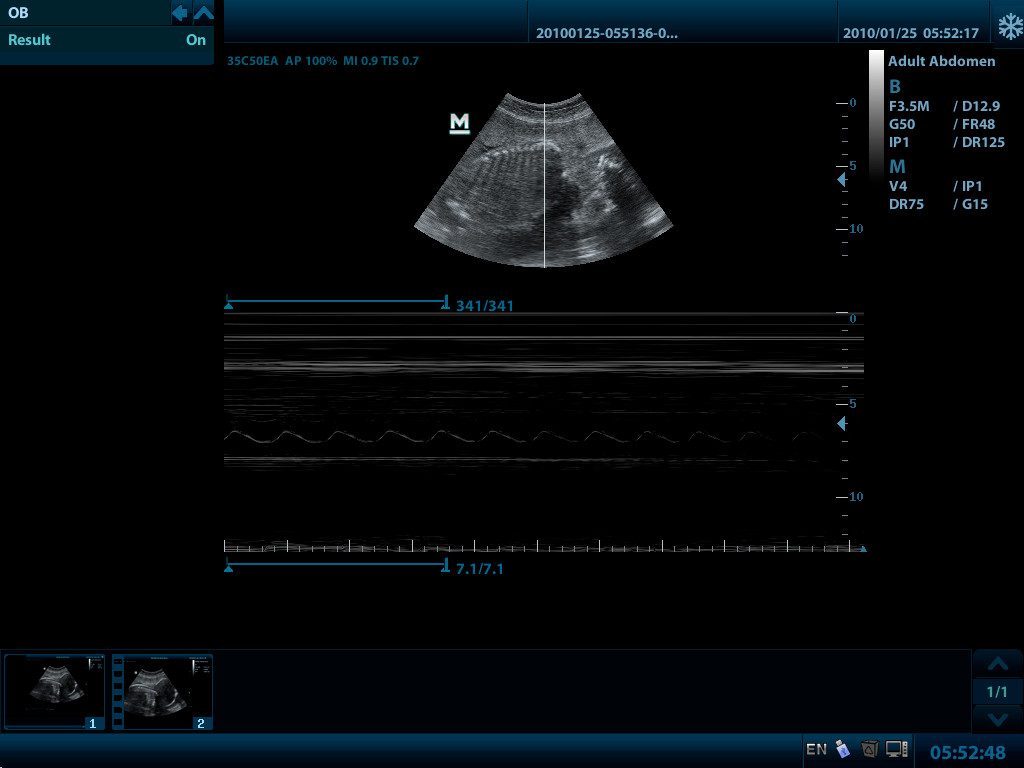

Mindray DP-50 – портативная цифровая ультразвуковая система с ЖК монитором 15 дюймов (1024Х768)

и встроенными аккумуляторными батареями (опция) позволяющими работать в автономном режиме до 2-х часов.

- THI - режим тканевой гармоники

DP-50 – портативный УЗИ сканер разработан на базе новой платформы X-treme engine, используемой в хорошо зарекомендовавших себя цветных сканерах с доплером моделей DC-3, DC-7, DC-6. Эта платформа открывает возможности для расширений до уровня цветных сканеров и совместимости с широким диапазоном периферийного оборудования. X-treme означает интеллект, высокую скорость обработки данных, многоуровневую передачу сигналов, а также возможность оптимизации изображения и модульного расширения.

Конвексный датчик 35C50EA (2.0/3.5/4.5/5.0/Н5.0/Н6.0) R50